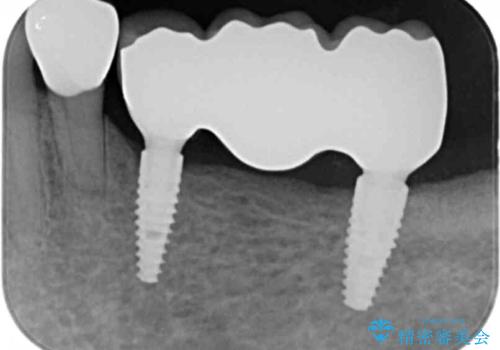

- 虫歯の多発、歯周病治療の治療を希望され、全体的な治療を提案した症例です。

重度の深い虫歯・歯周病の歯が散見されますので、まずは残せる歯と残せない歯の見極めを行い、残せる歯は歯周外科手術を用いて歯を可能な限り残すことを計画します。

長期的な予後を見込むには、虫歯の徹底的な除去・歯周ポケットの除去・噛み合わせの安定・適合の良い補綴物の要件を満たすことが重要です。

残せる歯と残すことが難しい歯の選別、ブリッジ・インプラントを適宜判断し補綴処置を行っていきます。